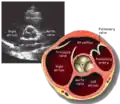

Parasternal short axis (PSAX)

Parasternal short axis at mid-LV showing papillary muscles

Parasternal short axis showing aortic valve

This view is obtained in the same window as the parasternal long, but with the probe rotated 90°. In this view, the aortic valve is seen in cross-section with the right ventricular inflow & outflow tracts visible with the tricuspid valve as well. Pulmonary valve is not visible in this view. Both the right and left atria are visible.

The standard PSAX view is at the level of the aortic valve, but moving the probe along the long-axis can review the LV outflow tract, LV at the base, and LV at the midsection.